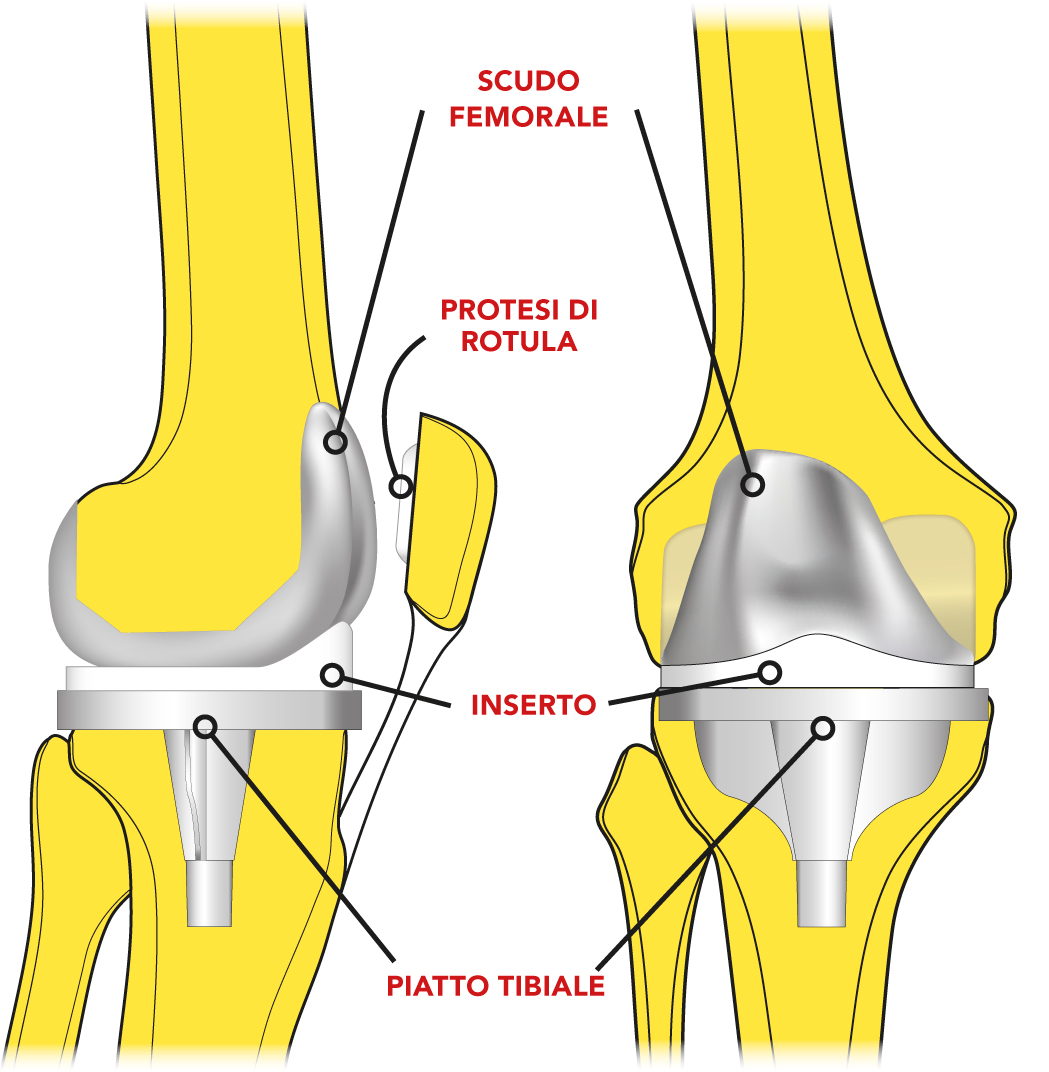

I pazienti con artrosi primitiva o con difetti assiali di lieve entità sono stati trattati mediante l’utilizzo di protesi cementate con inserto a stabilizzazione posteriore che consente un ottimale recupero della cinematica del ginocchio con basso rischio di usura delle componenti protesiche e di instabilità articolare.

Le ginocchia con gravi deviazioni assiali sono state trattate con protesi con inserti a stabilizzazione posteriore (a), semivincolate (b) o vincolate (c).

La tecnica chirurgica prevede diversi accessi scelti in base alle caratteristiche del ginocchio: accesso standard (47%) (d), sub-vastus (32%) e mid-vastus (18%) con artrotomia pararotulea mediale. In caso di gravi deformità in valgo è stato eseguito un acceso chirurgico standard con artrotomia pararotulea laterale (3%). L'impianto della protesi è guidato da un apposito strumentario che permette delle resezioni ossee precise per la correzione delle deformità assiali (e) e per l'impianto della protesi (f).